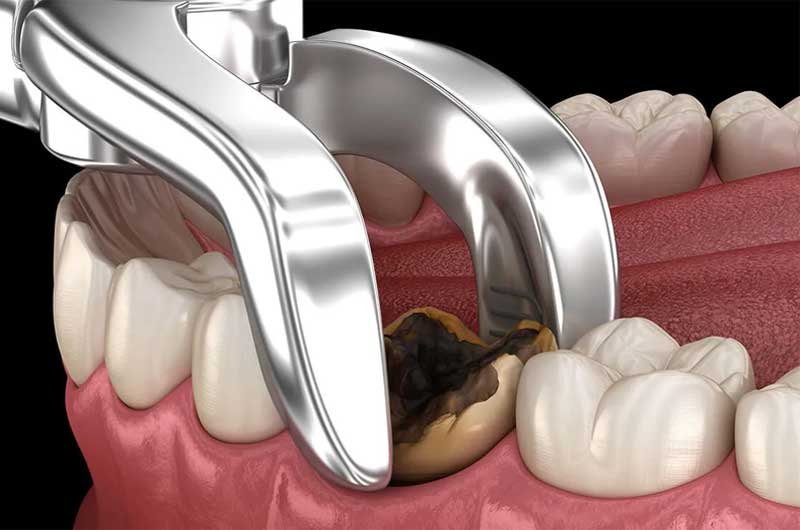

Nhổ răng

Một phương pháp khác để chấm dứt căn bệnh viêm tủy răng có mủ là tháo bỏ răng bị ảnh hưởng. Việc nhổ răng được khuyến nghị khi răng bị tổn thương nặng và các mô xung quanh bị nhiễm trùng đến mức không thể phục hồi.

Các tiến bộ trong kỹ thuật điều trị đã giảm bớt đau đớn trong quá trình này so với sự tưởng tượng của chúng ta. Vì vậy, bệnh nhân cần chú ý điều trị kịp thời để ngăn chặn các biến chứng nguy hiểm có thể xảy ra.